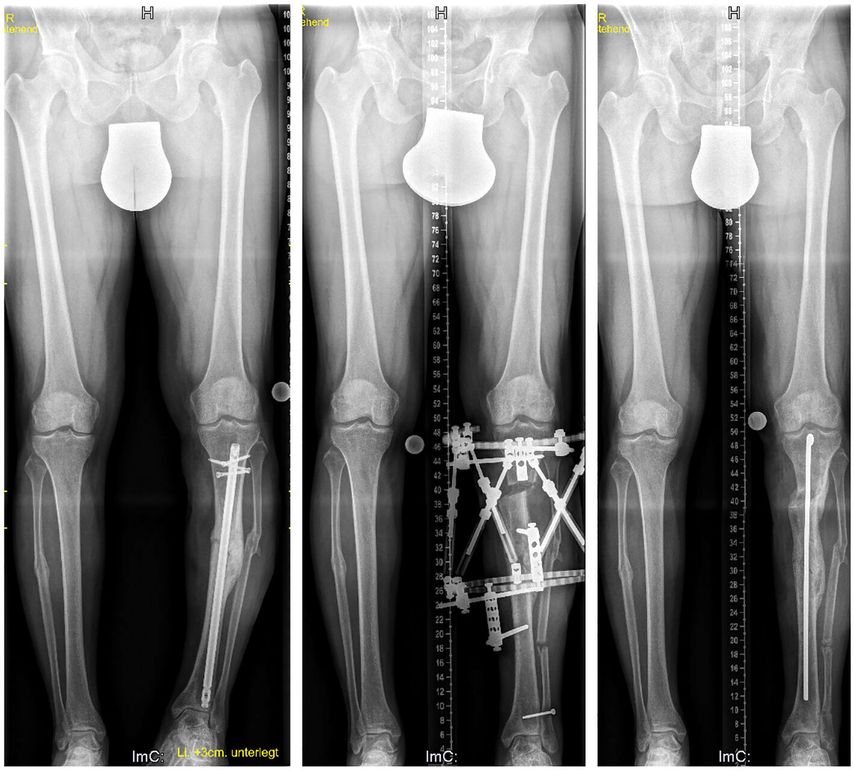

Auch an unserer Abteilung kommt der Hexapoden-Fixateur bei Patienten von 2 bis 92 Jahren zum Einsatz. Hauptindikation an unserer Abteilung sind Achskorrektur und Beinverlängerung im Kindes- und Jugendalter, wobei hier vor allem kongenitale Deformitäten (kongenitaler Femurdefekt, Fibulahemimelie, Tibiahemimelie, posteromediales Bowing) (Abb. 3), posttraumatische Deformitäten und Deformitäten im Rahmen von Syndromen oder metabolischen Erkrankungen (XLH) behandelt werden.

Abb. 3: Bei diesem 4-jährigen Patienten mit kongenitalem Femurdefekt (CFD) erfolgten eine Verlängerung und Achskorrektur am distalen Femur mittels TSF. Zusätzlich wurden die Retrotorsion am proximalen Femur und ein Teil der Varusfehlstellung akut korrigiert. Der Knieüberbau verhindert bei instabilem Kniegelenk bei angeborener Kreuzbandaplasie/Hypoplasie eine Subluxation des Gelenks. Das Knie wird in der Nacht in Streckung fixiert, um eine Kontraktur bei Verlängerung zu verhindern, welche in diesem Fall knapp über 5cm betrug. Um eine Fraktur des unreifen Kallus, wie sie bei CFD häufig ist, zu verhindern, erfolgte simultan mit dem Apparatabbau eine Fixierung mit Rush-Pin. Dieser wurde 9 Monate später nach Röntgenkontrolle wieder entfernt. Der rezidivierende Valgus, der bei CFD typisch ist, kann zwischen den Verlängerungsschritten mittels Wachstumslenkung einfach korrigiert werden

Bei Erwachsenen sind es ebenfalls erworbene und angeborene Fehlstellungen, wobei hier Pseudarthrosen (Abb. 4), infizierte Pseudarthrosen sowie nicht verheilte Arthrodesen am Fuß und Sprunggelenk hinzukommen. Bei der simplen Beinverkürzung ohne oder mit geringer Achsabweichung hat der Verlängerungsmarknagel (Precice®, Nuvasive Inc.) den externen Fixateur abgelöst. Dieser Verlängerungsmarknagel kann über einen antegraden Zugang am Oberschenkel ab dem 8.–10. Lebensjahr verwendet werden und über einen femoralen retrograden Zugang oder nach Fugenschluss an der Tibia eingesetzt werden.

Abb. 4: Dieser 42-jährige Patient erlitt eine offene Unterschenkelfraktur, die sich trotz initialen Fixateurs externe infizierte. Es erfolgten eine Lappenplastik und schließlich eine Osteosynthese mit Marknagelung. Bei der Vorstellung 4 Jahre nach dem initialen Trauma zeigten sich eine Varusfehlstellung und eine Beinverkürzung von 1,7 cm. Der Nagel wurde entfernt und eine Osteotomie proximal der ehemaligen Fraktur durchgeführt. Auch in diesem Fall wurde nach Apparatabbau ein Rush-Pin zur weiteren Stabilisierung eingebracht. Die Beinlänge und Beinachse konnten vollständig korrigiert werden